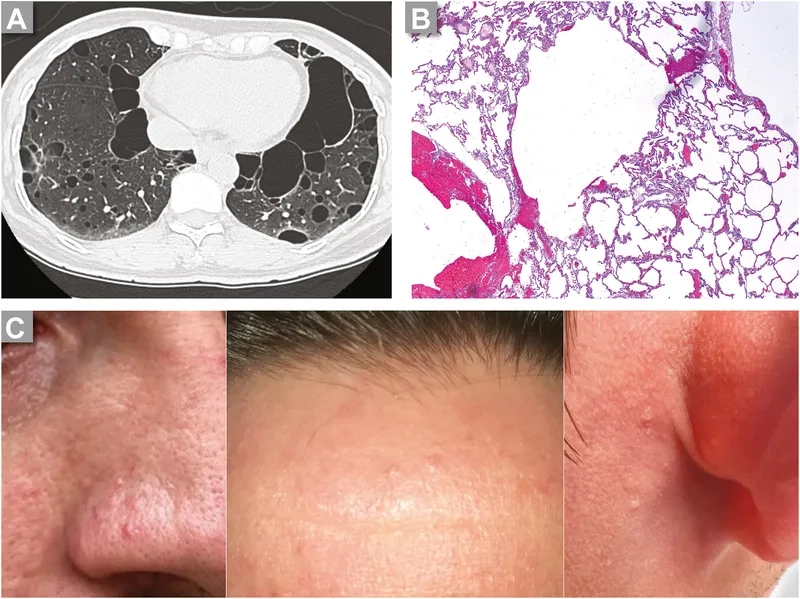

• Genetic mutations, particularly in the TSC1 or TSC2 genes, are a primary driver of the disease, leading to abnormal cell growth in the lungs.

• This condition can occur sporadically or in direct association with a genetic disorder known as tuberous sclerosis complex (TSC), which also involves benign tumors.

• Progressive shortness of breath in women, especially during physical activity or exertion, is the most common and defining of all LAM symptoms.

• Recurrent collapsed lungs (pneumothorax) and a milky fluid buildup around the lungs (chylothorax) are serious complications that often require immediate medical attention.

• Other potential signs include benign kidney tumors (angiomyolipomas), a persistent cough, chest pain, and fatigue, which can impact daily quality of life.